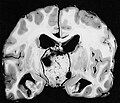

Gross

- Cystic mass filled with motor oil-like fluid.[5]

- May not be seen in the papillary variant of craniopharyngioma.

- Calcified - adamantinomatous type only.

- Solid & cystic.